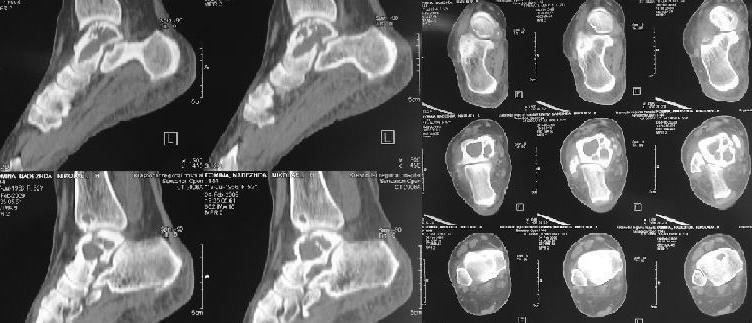

Киста таранной кости

Здраствуйте коллеги! К нам обратилась пациентка 52 лет с болями в области голеностопного сусатва.

Со слов болеет в течение 5 лет. По м\ж лечилась консервативно. Выполнили Rg- и KT- . Выявлена киста таранной и большеберцовой костей. Взята открытая биопсия таранной кости(результат пока не готов). Визуально в тараной кости полость, без какого либо содержимого.

Какую тактику лечения вы посоветуете? Выполнить костную аутопластику (с сомнительным результатом) или же сразу выполнить астрогалэктомию? Или же другие варианты?